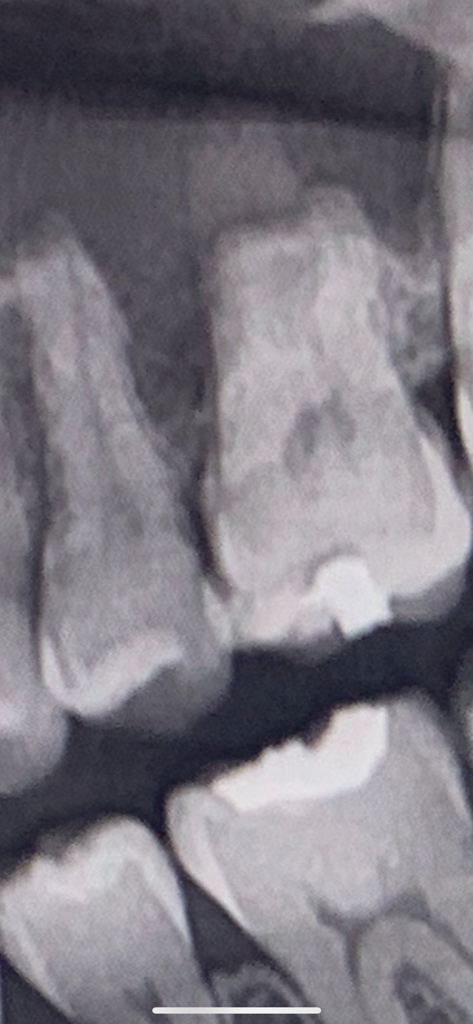

이거 인접면 충치인가요?궁금합니다.

첫번째 사진은 2020년이고

2번째 사진은 2023년9월사진입니다.

상악부분에 의심되는 충치가 있나요?

• 1번 째 사진

• 2번 째 사진

인접면 우식의 경우 인접한 두 치아가 겹치지 않게 찍은 사진이 필요합니다

현재사진으로서는 인접면 우식에 대한 정확한 판단은 어렵고요

증상과 관련해서는 기존에 씹는면 떼운부위가 살짝 깨졌거나 부러져 나가지는 않았는지 확인해봐야 합니다 틈이 있다면 그 사이로 침이 들어가 불편한 느낌이 생길 수 있습니다

찬것, 뜨거운 음식을 먹을때 괜찮고 씹을때도 괜찮다면 치아 사이에 음식물이 끼어(식편압입) 잇몸에 염증이 생겨서 불편한 증상이 나타날수도 있습니다 사진상으로 치아 사이 컨택이 아주 깔끔하지는 않을 것으로 추측됩니다 치실이나 치간칫솔 통해서 해당부위 위생관리를 잘해주시면 증상이 완화될수도 있겠습니다

일단은 약간 인접면 충치가 의심되지만 일단 욱신거린다면 충치보다는 잇몸이 안좋아서 그럴가능성이 잇으니 잇몸치료를 먼저 받아보세요.